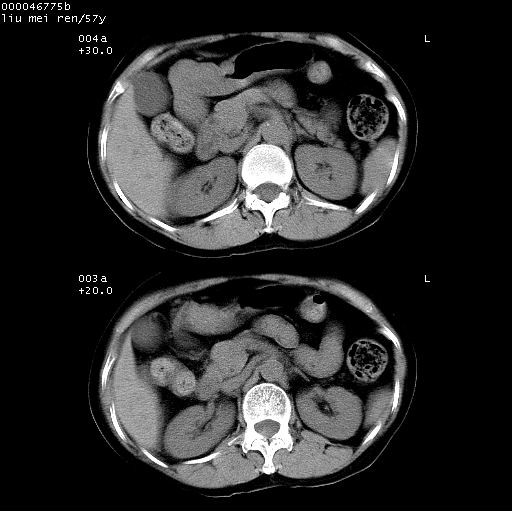

患者 女,57岁。因车祸受伤,其家属要求行“全身ct检查”。平素健康。

胸部ct轴位平扫(层厚10mm,螺距1.5,重建间隔10mm),图像如下: